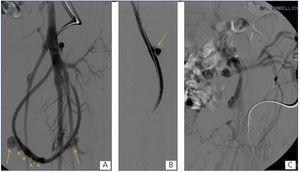

Presentamos el caso de una paciente de 46 años de edad con insuficiencia renal crónica, en hemodiálisis trimestral desde hace 23 años, secundaria a uropatía obstructiva, portadora de un loop femoral izquierdo de 21 meses de uso que tenía una oclusión del drenaje venoso a nivel ilíaco que ocasionaba edema del miembro inferior y tres pseudoaneurisma en rango terapéutico (figura 1). Uno de estos pseudoaneurismas presentaba un sangrado activo. Los tres pseudoaneurismas y la oclusión de la vena ilíaca primitiva izquierda fueron tratados de forma endovascular bajo anestesia local. El pseudoaneurisma que tenía el sangrado activo se excluyó con un stent cubierto y los dos restantes se embolizaron de forma percutánea mediante la inyección de trombina asistida con balón para evitar la trombosis de la prótesis. El eje venoso ilíaco se recanalizó y trató con balones de angioplastia; en los controles angiográficos finales se observó ausencia de los pseudoaneurismas con permeabilidad de la prótesis y del drenaje venoso ilíaco con desaparición de la circulación colateral (figura 2), no habiéndose presentando complicaciones relacionadas con la intervención.

Figura 1. Fistulografías

Figura 2. Stent, imágenes fluoroscópicas y fistulografía